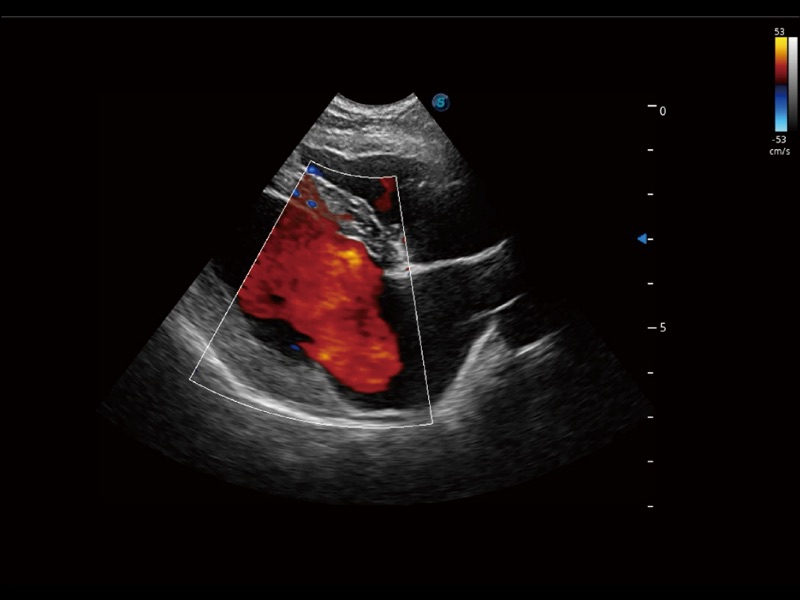

实时用颜色表示心肌组织运动,观察和定量组织的运动情况,对快速检测与评估心肌的灌注和活性、电传导及心肌收缩和舒张功能等均能提供重要的诊断信息。